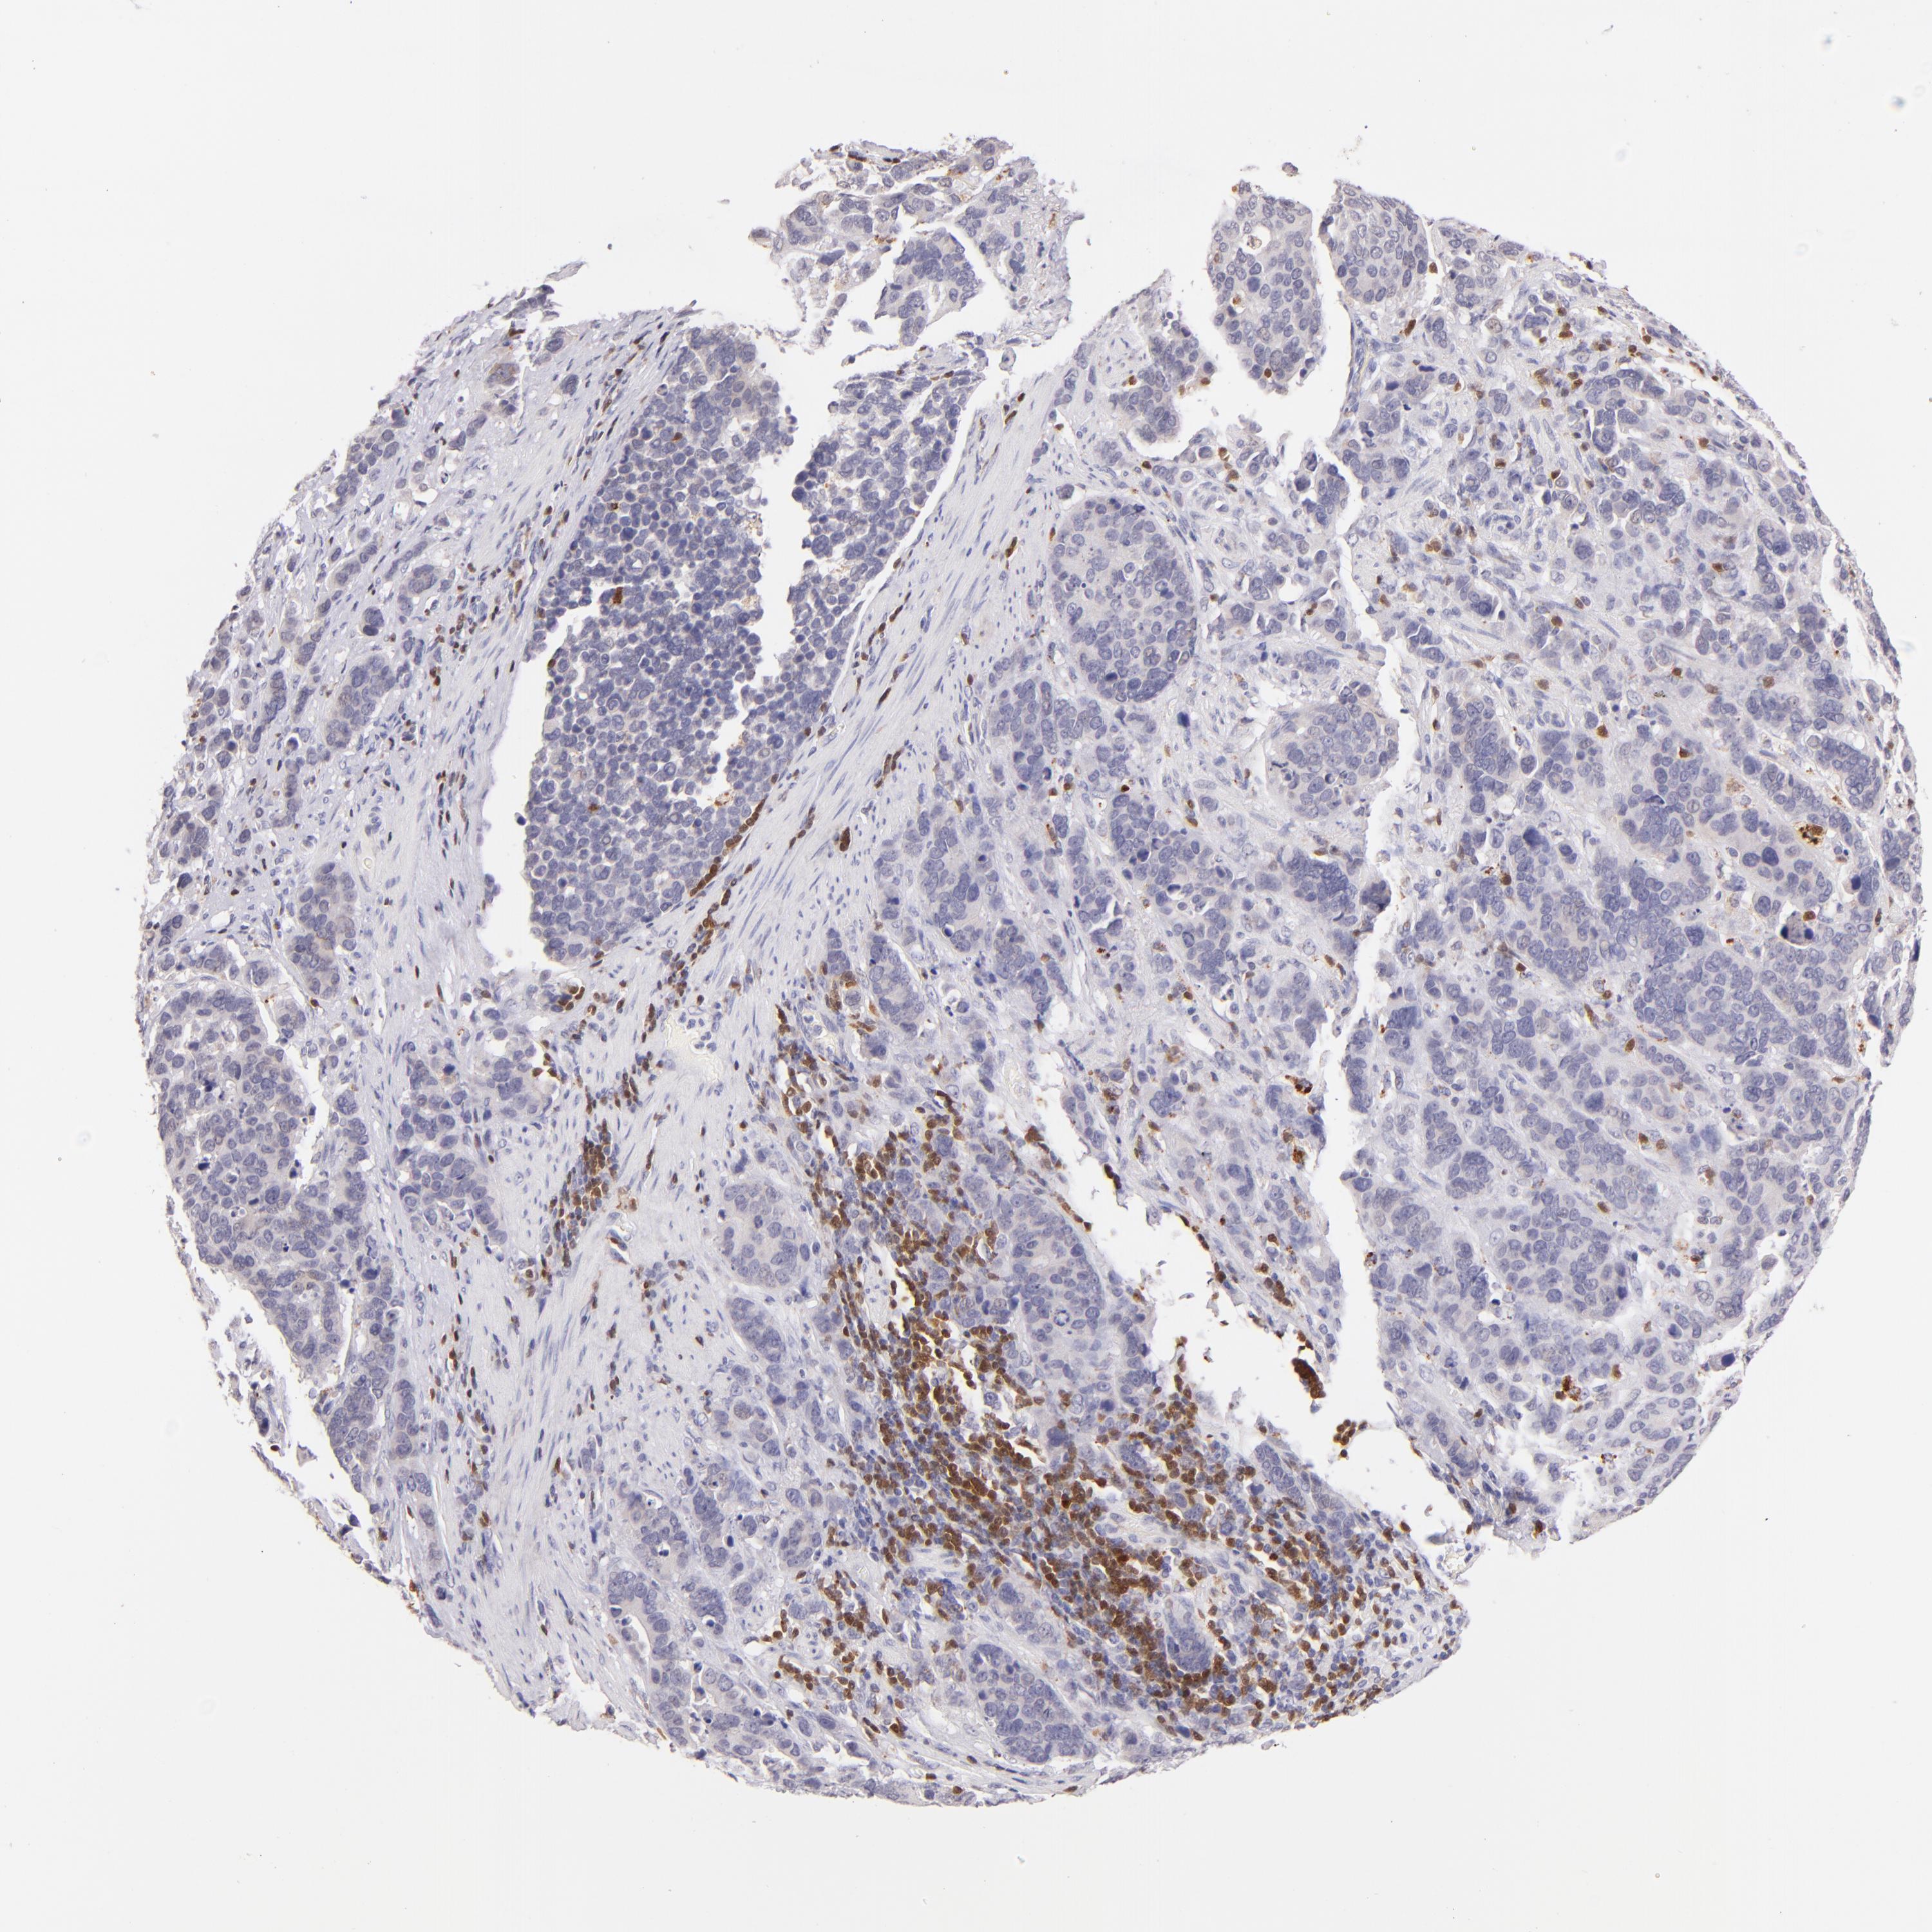

STOMACH CANCER - Protein expressioni

A mouse-over function shows sample information and annotation data. Click on an image to view it in a full screen mode. Samples can be filtered based on level of antibody staining by selecting one or several of the following categories: high, medium, low and not detected. The assay and annotation is described here.

Note that samples used for immunohistochemistry by the Human Protein Atlas do not correspond to samples in the TCGA dataset.

Antibody stainingi

Antibody staining in the annotated cell types in the current human tissue is reported as not detected, low, medium, or high, based on conventional immunohistochemistry profiling in selected tissues. This score is based on the combination of the staining intensity and fraction of stained cells.

Each image is clickable and will lead to virtual microscopy that enables deeper exploration of all samples and also displays staining intensity scores, fraction scores and subcellular localization as well as patient and tissue information for each sample.

Antibody HPA003134

Antibody CAB002625

Staining

High

Medium

Low

Not detected

Intensity

Strong

Moderate

Weak

Negative

Quantity

>75%

75%-25%

<25%

None

Location

Nuclear

Cytoplasmic/membranous

Cytoplasmic/membranous,nuclear

Adenocarcinoma, NOS